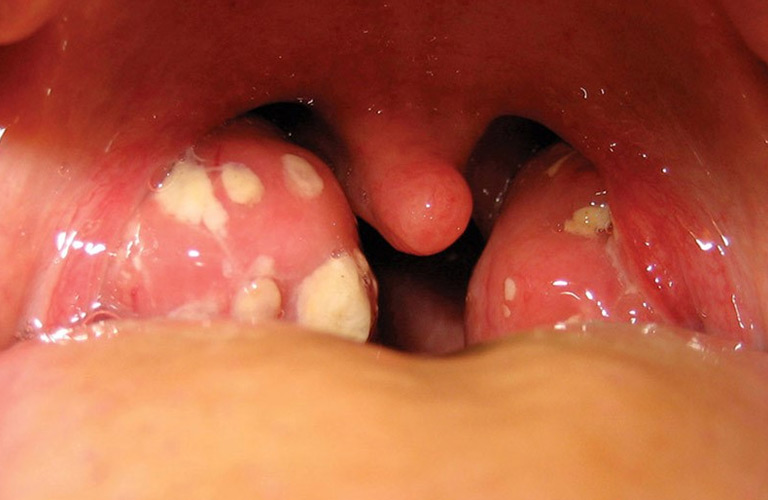

Viêm amidan mủ ở trẻ em là tình trạng viêm nhiễm nặng ở amidan, do vi khuẩn gây ra, thường kèm theo mủ trắng hoặc vàng trong hốc amidan. Bệnh lý này phổ biến ở trẻ em, đặc biệt là trong những mùa lạnh khi hệ miễn dịch của trẻ yếu hơn. Tuấn tôi đã gặp không ít trường hợp bà con mang con đến khám khi thấy trẻ đau họng, khó nuốt, hoặc sốt cao. Khi đó, viêm amidan mủ có thể là nguyên nhân chính dẫn đến những triệu chứng này. Tuy nhiên, không phải tất cả các trường hợp đau họng đều là viêm amidan mủ, do đó cần sự chẩn đoán chính xác từ bác sĩ để có phương pháp điều trị kịp thời.

- Có mủ trắng hoặc vàng trong hốc amidan, dễ nhận thấy khi mở miệng trẻ.